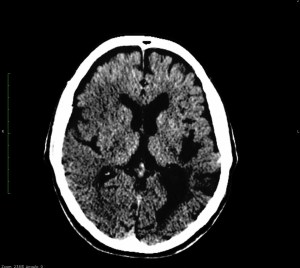

Se realiza un TC de cráneo sin contraste, estos son los hallazgos:

Esta imágen plantea dudas, puede ser una masa o un foco de sangrado, es más, si de esta segunda imagen asumimos que la zona de densidad aumentada corresponde a un sangrado, la pregunta a realizarse ahora es ¿de qué tipo? ¿Es un sangrado intraparenquimatoso, una transformación hemorrágica de un infarto o es otra cosa?